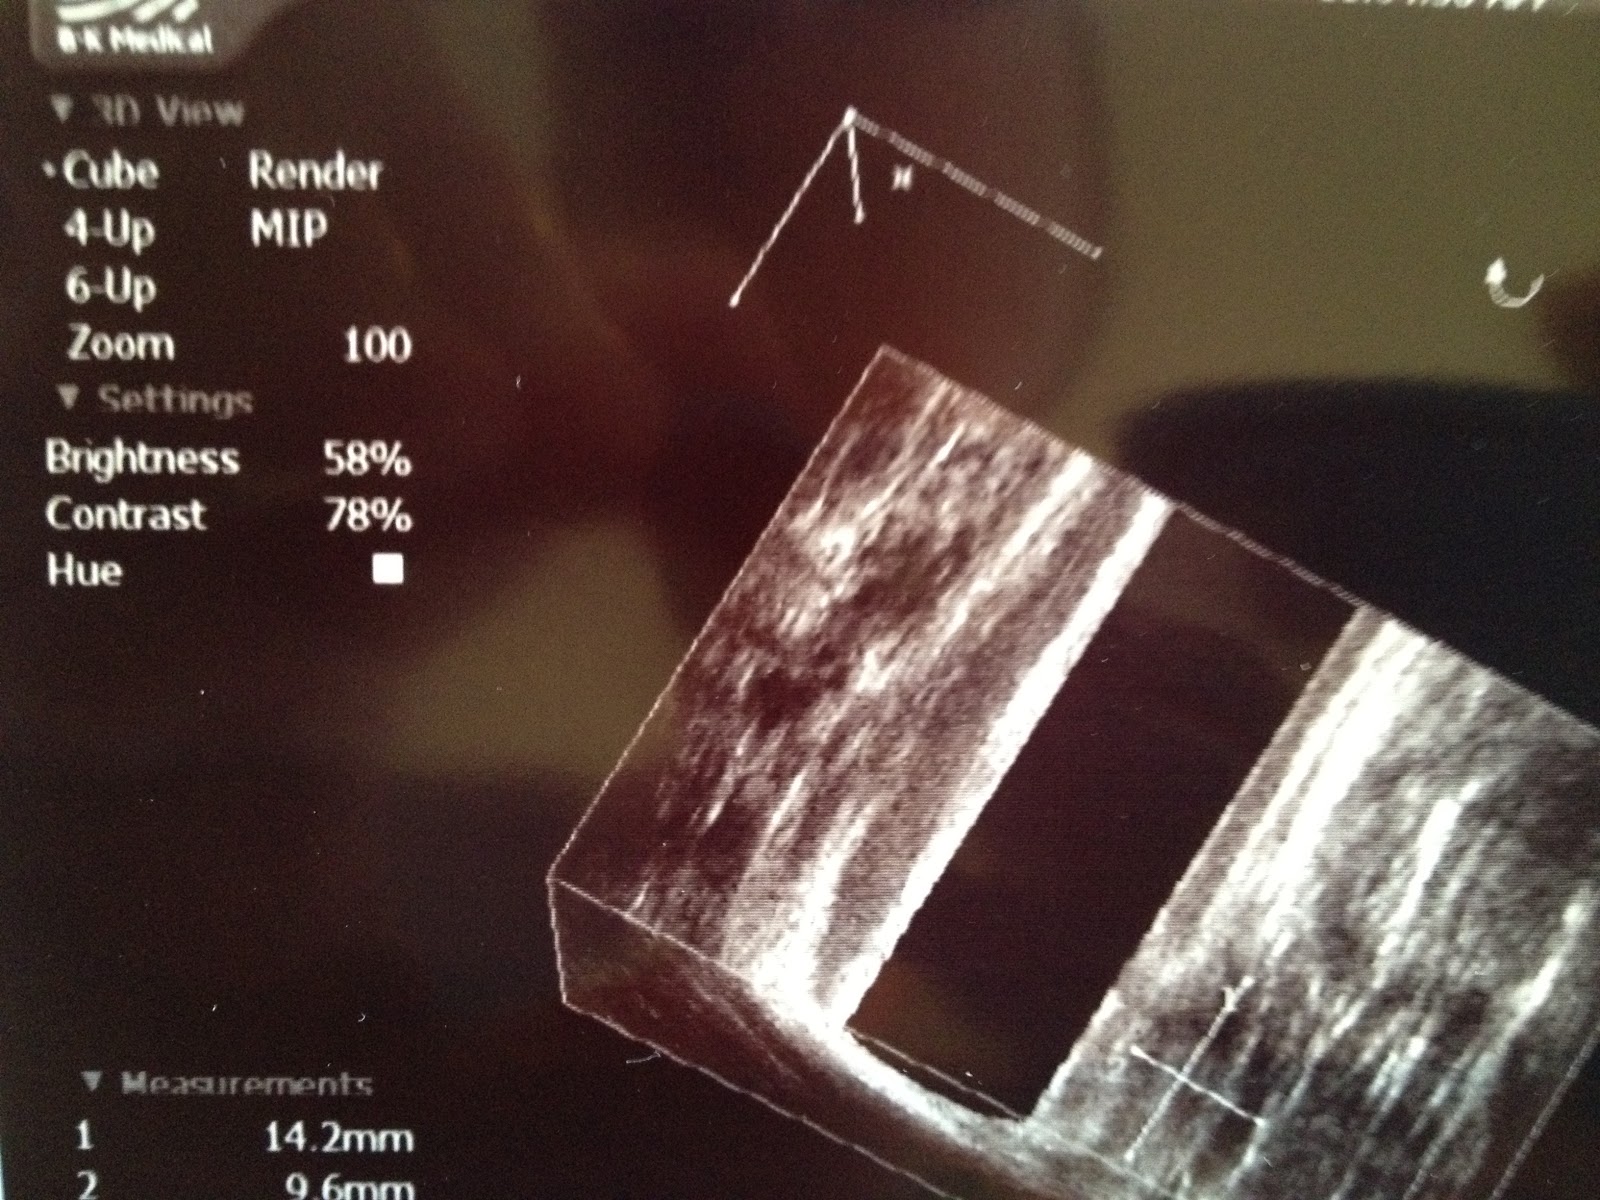

Looks pretty innocuous until you really pay attention.  Then you realize that brightness, contrast, and hue aren't really all that important when you looking at a cutaway diagram of the inside of my ass.  You might think, "Scooter, this is way too private."  But there were three individuals of two nationalities and three ethnic backgrounds in the room during the scan, and two others during the pre-scan check, so no matter how many people check out this picture, it's not nearly as personal as the five individuals who took a close up, in the flesh, look.

I found this fairly interesting.  This one is the one where you can't really see the problem.  This is pretty much what everyone's looks likes when it's vaguely healthy.  Nothing surprising.  No parasites.  Nothing stuck up there.  It looks good.

And this is after they take a needle to me and inject hydrogen peroxide.  See where the little crosshairs are, lower right, if you compare photos, you'll see a solid white area which is where the fistula occurred (thanks Regions) and where they cut into it yesterday.  Pretty harmless looking for such a pain in the ass.